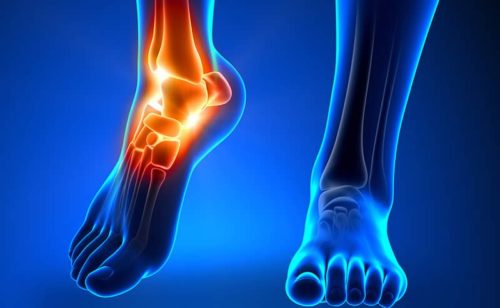

Голеностопом называют суставное соединение костей стопы с большой и малой берцовых костей. Этот сустав, в отличие от плечевого, и коленного, очень плотный и малоподвижный, что с одной стороны, надежно удерживает кости в положенном для них месте и выдерживает существенные нагрузки – на него приходится вес всего тела организма. Однако та-же, малая подвижность голеностопа, часто приводит к его травмированию – к вывихам, сопровождающимися опухолью сустава, растяжениям, а после, даже к разрыву связок. Высокая степень риска травматизма голеностопа дополняется еще одним негативом – сложностью лечения и длительной восстановительной реабилитацией.

Голеностоп имеет сложное строение, позволяющее ему ловко двигаться, принимая удобное и безопасное положение во время движения человека. Четкое взаимодействие сустава, мышц и связок обеспечивает достаточную амплитуду движений, что позволяет не создавать ограничений во время ходьбы, бега, других способов передвижения. Но такая сложная структура голеностопа часто становится причиной разного рода травм, среди которых 20% приходится именно на растяжение или разрыв связок голеностопа.